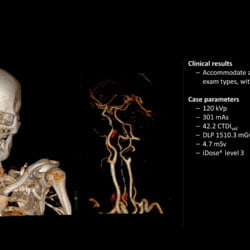

Incisive CT de 64 canais e 128 cortes

Especificações Técnicas do Tomógrafo Philips Incisive CT

| Tipo de tubo | Tubo vMRC Cerâmico |

| Capacidade do tubo | 8 MHU |

| Configuração de kVp | 70, 80, 100, 120, 140 kV |

| Tamanho do bore | 72 cm |

| Cortes | até 128 cortes |

| Cobertura | 40 mm |

| Potência do gerador | 80 kW |

| Velocidade de rotação | até 0,35 s |